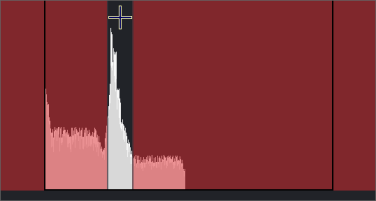

Window/Level Region of Interest Histogram

The small arrow at the right of the field values at the left end of the Window/Level toolbar is a dropdown. Select the down arrow  at the right end to reveal a histogram.

at the right end to reveal a histogram.

Click and hold on the + sign near the center of the histogram and drag in different directions to change the W and L numbers. The image will change accordingly.